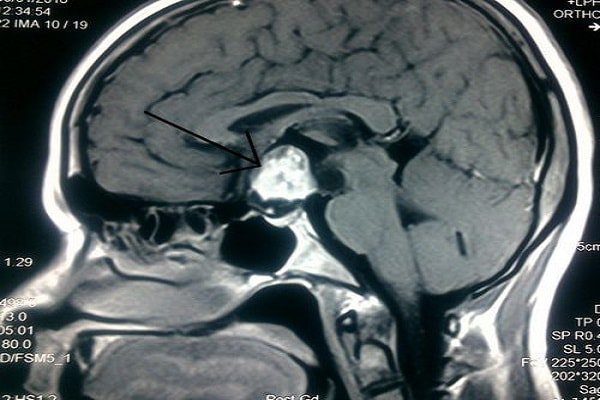

- Phát hiện được các tổn thương có kích thước nhỏ tại tuyến yên nhờ khả năng tạo ảnh chi tiết, có độ tương phản cao. Hình ảnh tuyến yên thu được khi chụp cộng hưởng từ tuyến yên rõ nét hơn rất nhiều lần khi chụp cộng hưởng từ sọ não.